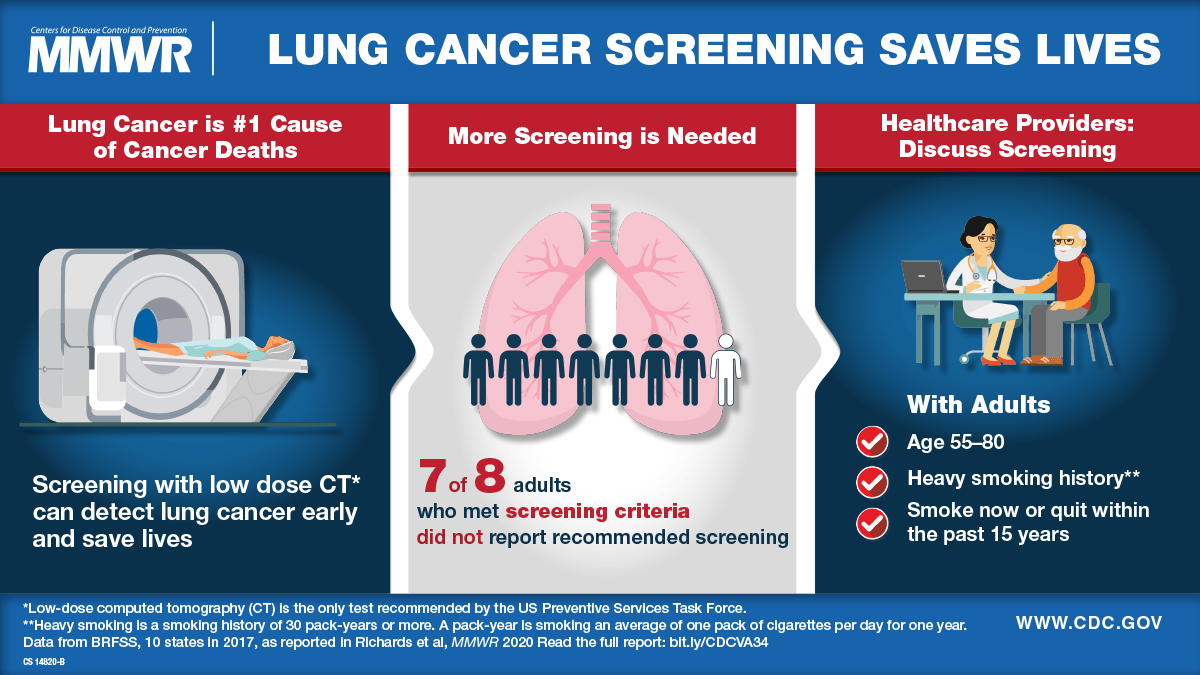

Reducing or eliminating occupational exposure to lung carcinogens. Screening is recommended if you’re at high risk. Smoke from other people’s cigarettes, cigars, or pipes is called secondhand smoke.

Lung cancer is cancer that starts in your lungs. The most important thing you can do to prevent lung cancer is to not start smoking, or to quit if you smoke. Lung cancer patient and advocate jill feldman takes pills at home that shrink tumors by blocking a signal that tells cancer cells to grow.

People with small cell lung cancer are usually treated with radiation therapy and chemotherapy. Changing lifestyle or eating habits. It is the leading cause of cancer death among men and women.